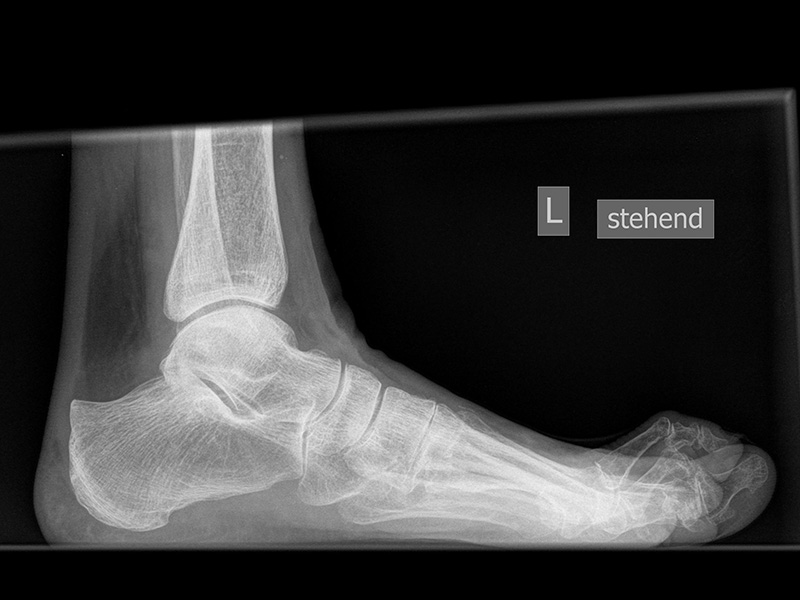

Fuß seitlich mit Belastung

Positionierung:

• Der Patient steht auf beiden Füßen mit gleichmäßiger Lastverteilung.

• Der zur Röntgen der Fuß wird längs des Films positioniert.

• Die Kassette steht senkrecht zum Boden, medial dem Fuß anliegend.

• Der Zentralstrahl wird von lateral nach medial zentriert auf das Kalkaneokuboidalgelenk knapp cranial der Os metatarsale V Basis ausgerichtet.

• Die Röntgenröhre steht 0° horizontal.

Kennzeichen des Röntgenbildes:

• Standardabbildung des Fußes zusammen mit der belasteten d.-p. Aufnahme und der unbelasteten 45° Pronationsaufnahme.

• Überblick über die Fußanatomie und Fußstatik.

• Die seitliche Aufnahme liefert Informationen zur Stabilität des Längsgewölbe und zu den Achsen von Talus, Kalkaneus und Metatarsale I.

• Die Aufnahme wird eingesetzt zur Darstellung von freien Gelenkkörpern sowie knöchernen Veränderungen am Achillessehnenansatz oder der Plantarfaszie.

Besondere Bemerkungen zum Beispielbild:

• Schwere Hallux valgus Deformität.

• Die Sesambeine sind luxiert, ebenso das Großzehengrundgelenk. Luxation des Metatarsophalangealgelenks II.

• Degenerative Veränderungen der tarsometatarsalen (TMT) Gelenkreihe, betont TMT II und III.